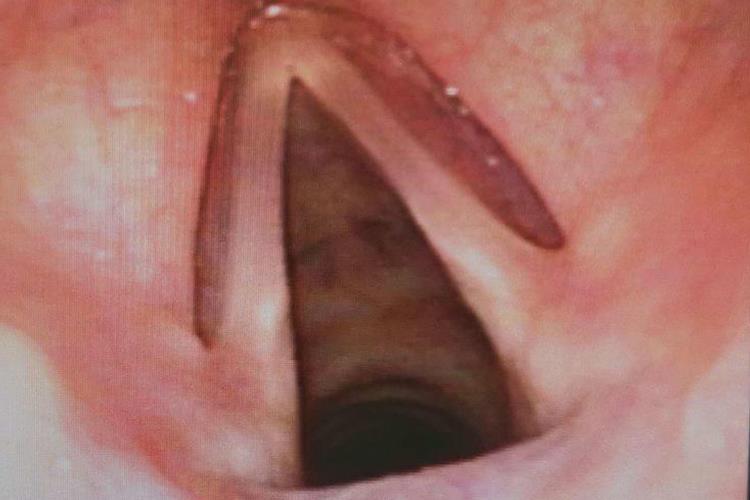

宝宝正常的喉咙需借助喉镜观察,可见其与周围组织相似的粉红色黏膜。

喉咙主要由软骨及其附近的韧带和肌肉组成,以软骨为基础,关节、韧带和筋膜为连结,喉肌作动力,喉黏膜内衬喉腔。宝宝正常的喉咙通过喉镜主要可观察到粉红色的黏膜,吸气时会出现类似等腰三角形的洞。